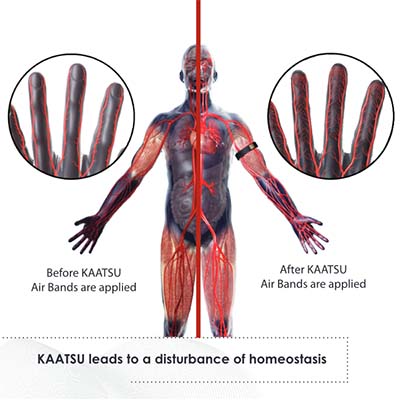

How KAATSU Works

KAATSU AirBands apply moderate compression in short durations on the upper arms or upper legs. The pneumatic bands are controlled by the main KAATSU unit. This temporary and rhythmic compression leads to the safe engorgement of the limbs with blood. This causes a cascade of natural beneficial physiological reactions in the body.

Dr. Yoshiaki Sato, inventor of KAATSU, is the pioneer of Blood Flow Moderation training. KAATSU was tested for a decade on 7000 cardiac patients at Tokyo University Hospital and was found to be safe when used appropriately. KAATSU’s equipment and protocols makes it the safest product in its class. Learn More >>